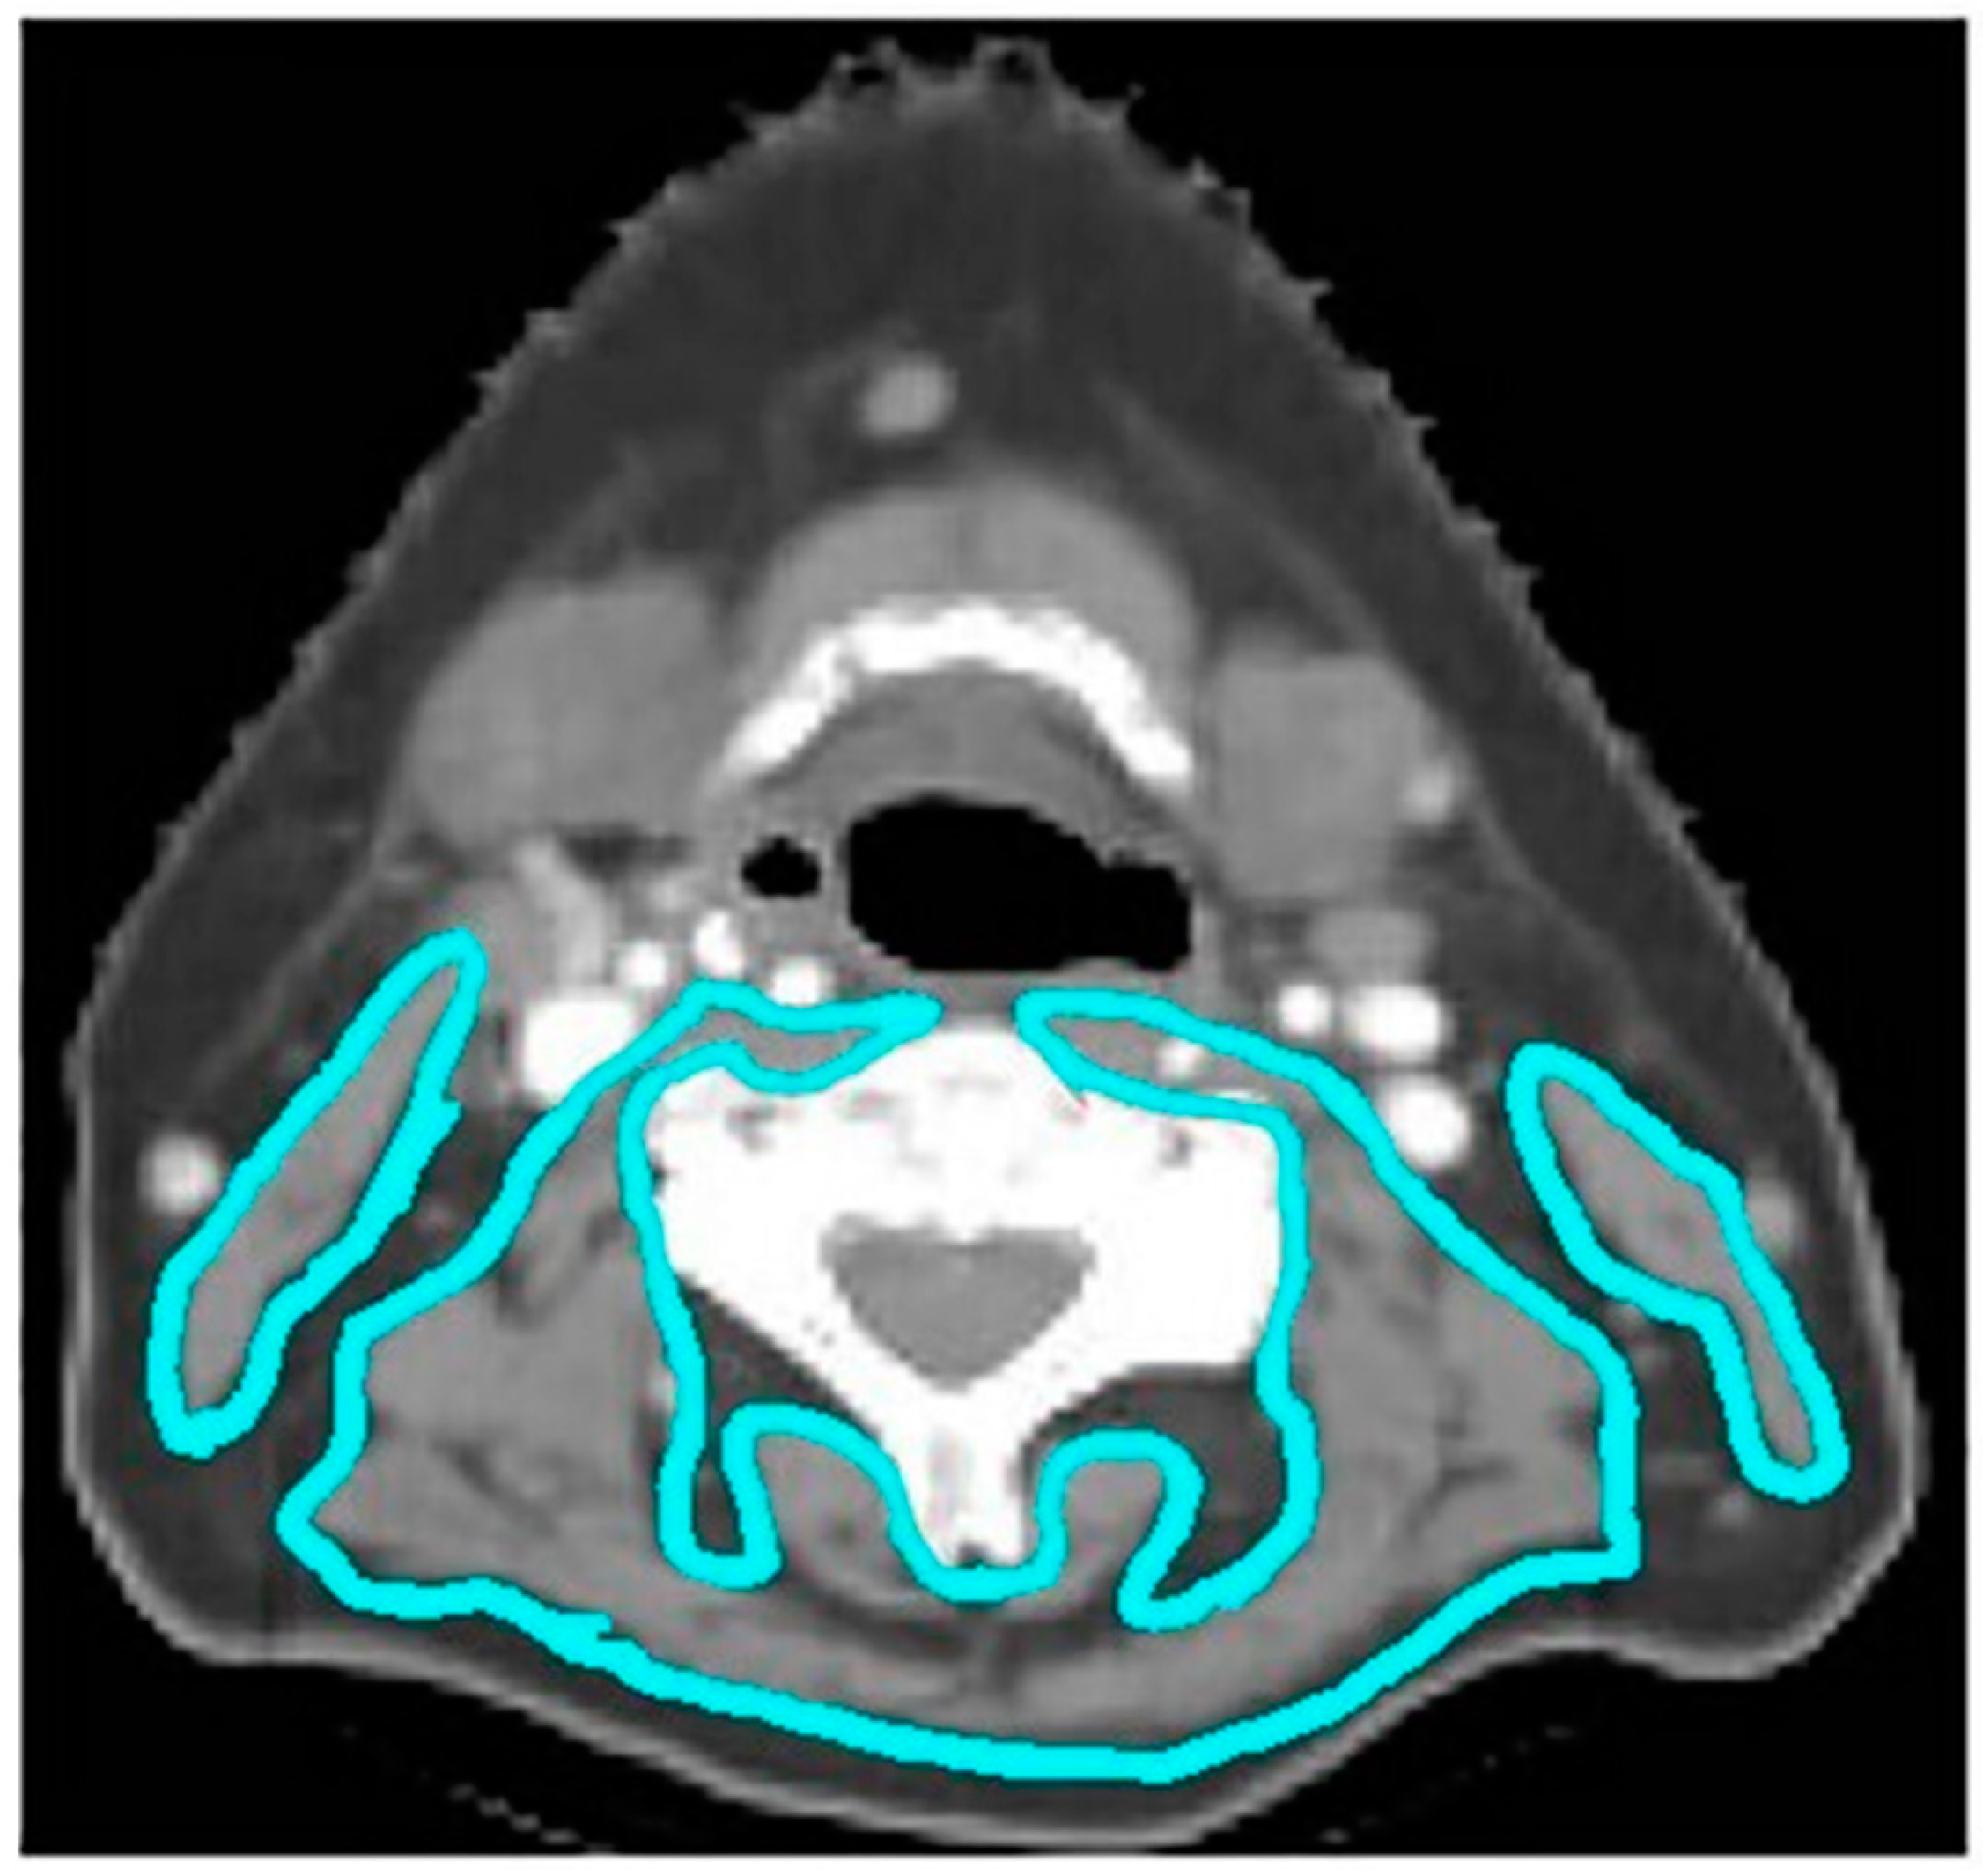

2.3. Body Composition Measurement

- Gomez-Perez, S.L.; Haus, J.M.; Sheean, P.; Patel, B.; Mar, W.; Chaudhry, V.; McKeever, L.; Braunschweig, C. Measuring Abdominal Circumference and Skeletal Muscle From a Single Cross-Sectional Computed Tomography Image: A Step-by-Step Guide for Clinicians Using National Institutes of Health ImageJ. J. Parenter. Enter. Nutr. 2015, 40, 308–318. [Google Scholar] [CrossRef] [Green Version]

- Swartz, J.E.; Pothen, A.J.; Wegner, I.; Smid, E.J.; Swart, K.M.; de Bree, R.; Leenen, L.P.; Grolman, W. Feasibility of using head and neck CT imaging to assess skeletal muscle mass in head and neck cancer patients. Oral Oncol. 2016, 62, 28–33. [Google Scholar] [CrossRef]